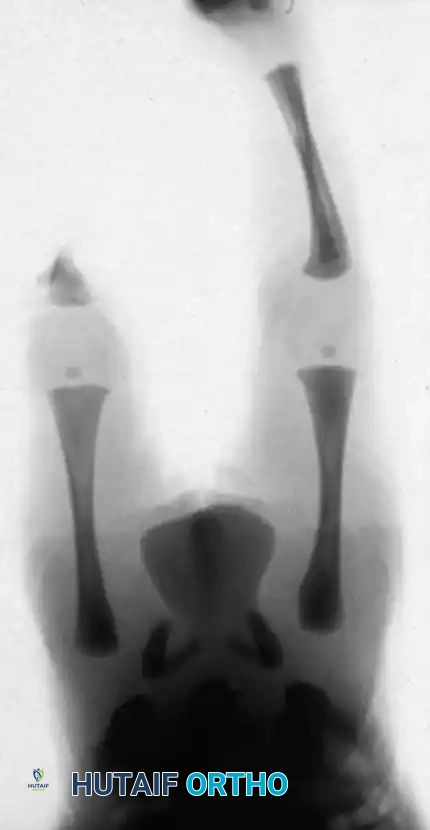

This condition represents a broad spectrum of deformities, ranging from the total absence of the tibia (the most severe form) to mild hypoplasia of the tibia (the least severe form). The incidence is exceedingly rare, estimated at one in 1 million live births, and the condition presents bilaterally in approximately 30% of affected patients.

- Type 1A Deformity: There is complete radiographic absence of the tibia and a hypoplastic distal femoral epiphysis compared with the contralateral normal side.

- Type 1B Deformity: There is no radiographic evidence of an ossified tibia; however, the distal femoral epiphysis appears more normal in size and shape. This distinction is critical because Type 1B deformities possess a proximal tibial cartilaginous anlage that can be expected to ossify over time. Modern imaging techniques, such as high-resolution ultrasound and MRI, are mandatory to identify this cartilaginous anlage.

- Type 2 Deformity: A proximal tibia of varying size is present and ossified at birth. The fibula is usually normal in size, but the fibular head is proximally dislocated.

- Type 3 Deformity: The proximal tibia is not radiographically visible, but the distal tibial epiphysis is present. This is an exceptionally rare variant. The distal femoral epiphysis is usually well-formed, but the upper end of the fibula is proximally dislocated, leading to profound knee instability.

- Type 4 Deformity: The tibia is shortened, and there is proximal migration of the fibula with distal tibiofibular diastasis. This rare deformity is also referred to as congenital diastasis of the ankle joint. The distal tibial epiphysis may be entirely absent.